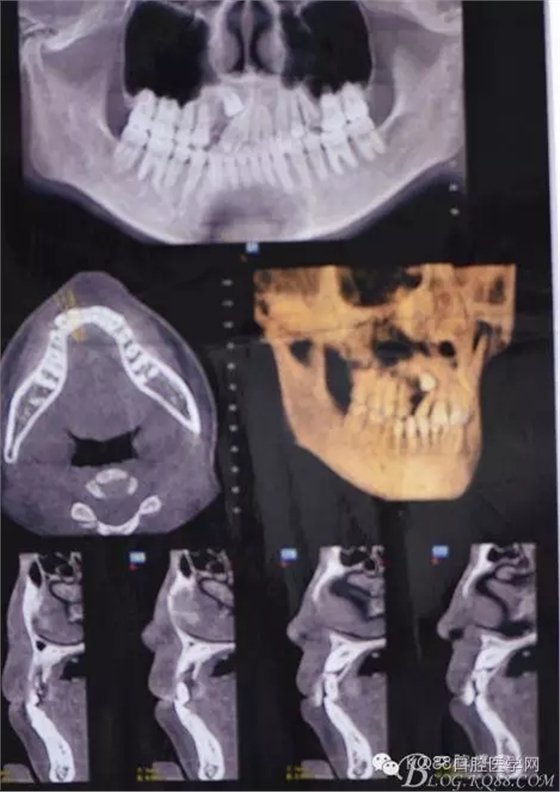

患者、女、高xx、17歲,主訴:外院轉(zhuǎn)診要求拔除埋伏牙。??茩z查:53殘根滯留、牙根斷面位于齦下,cbct檢查:13高位埋伏,牙冠壓迫12牙根的遠中面,牙根未見吸收,經(jīng)我院正畸科會診,建議拔除13、53,然后再正畸治療?;颊咄庵委煼桨福g前簽知情同意書。 拔牙過程: 圖1.術前的cbct檢查:13位于12遠中根尖區(qū),13牙根接近上頜竇、53牙根滯留。 圖2.口內(nèi)觀:53滯留、牙根斷面位于齦下,12牙冠唇傾。 圖3.合面觀:12畸形舌側(cè)窩、腭側(cè)沒有明顯隆起 圖4.首先拔除53,然后在23唇側(cè)區(qū)域的前庭溝處的黏膜做弧形切口 圖5. 翻瓣 圖6.去骨 圖7.暴露出13牙冠 圖8.高速渦輪機分牙、目的是盡量少去骨。 圖9. 從頸部截分13 圖10. 13牙冠頸部分牙情況 圖11.再把牙冠分成近中、遠中兩部分。 圖12.取出13牙冠 圖14.取出13牙根 圖15.取出的13的牙根 圖16.拔除13牙后形成的拔牙創(chuàng)。 圖17.拔除的13. 圖18.縫合